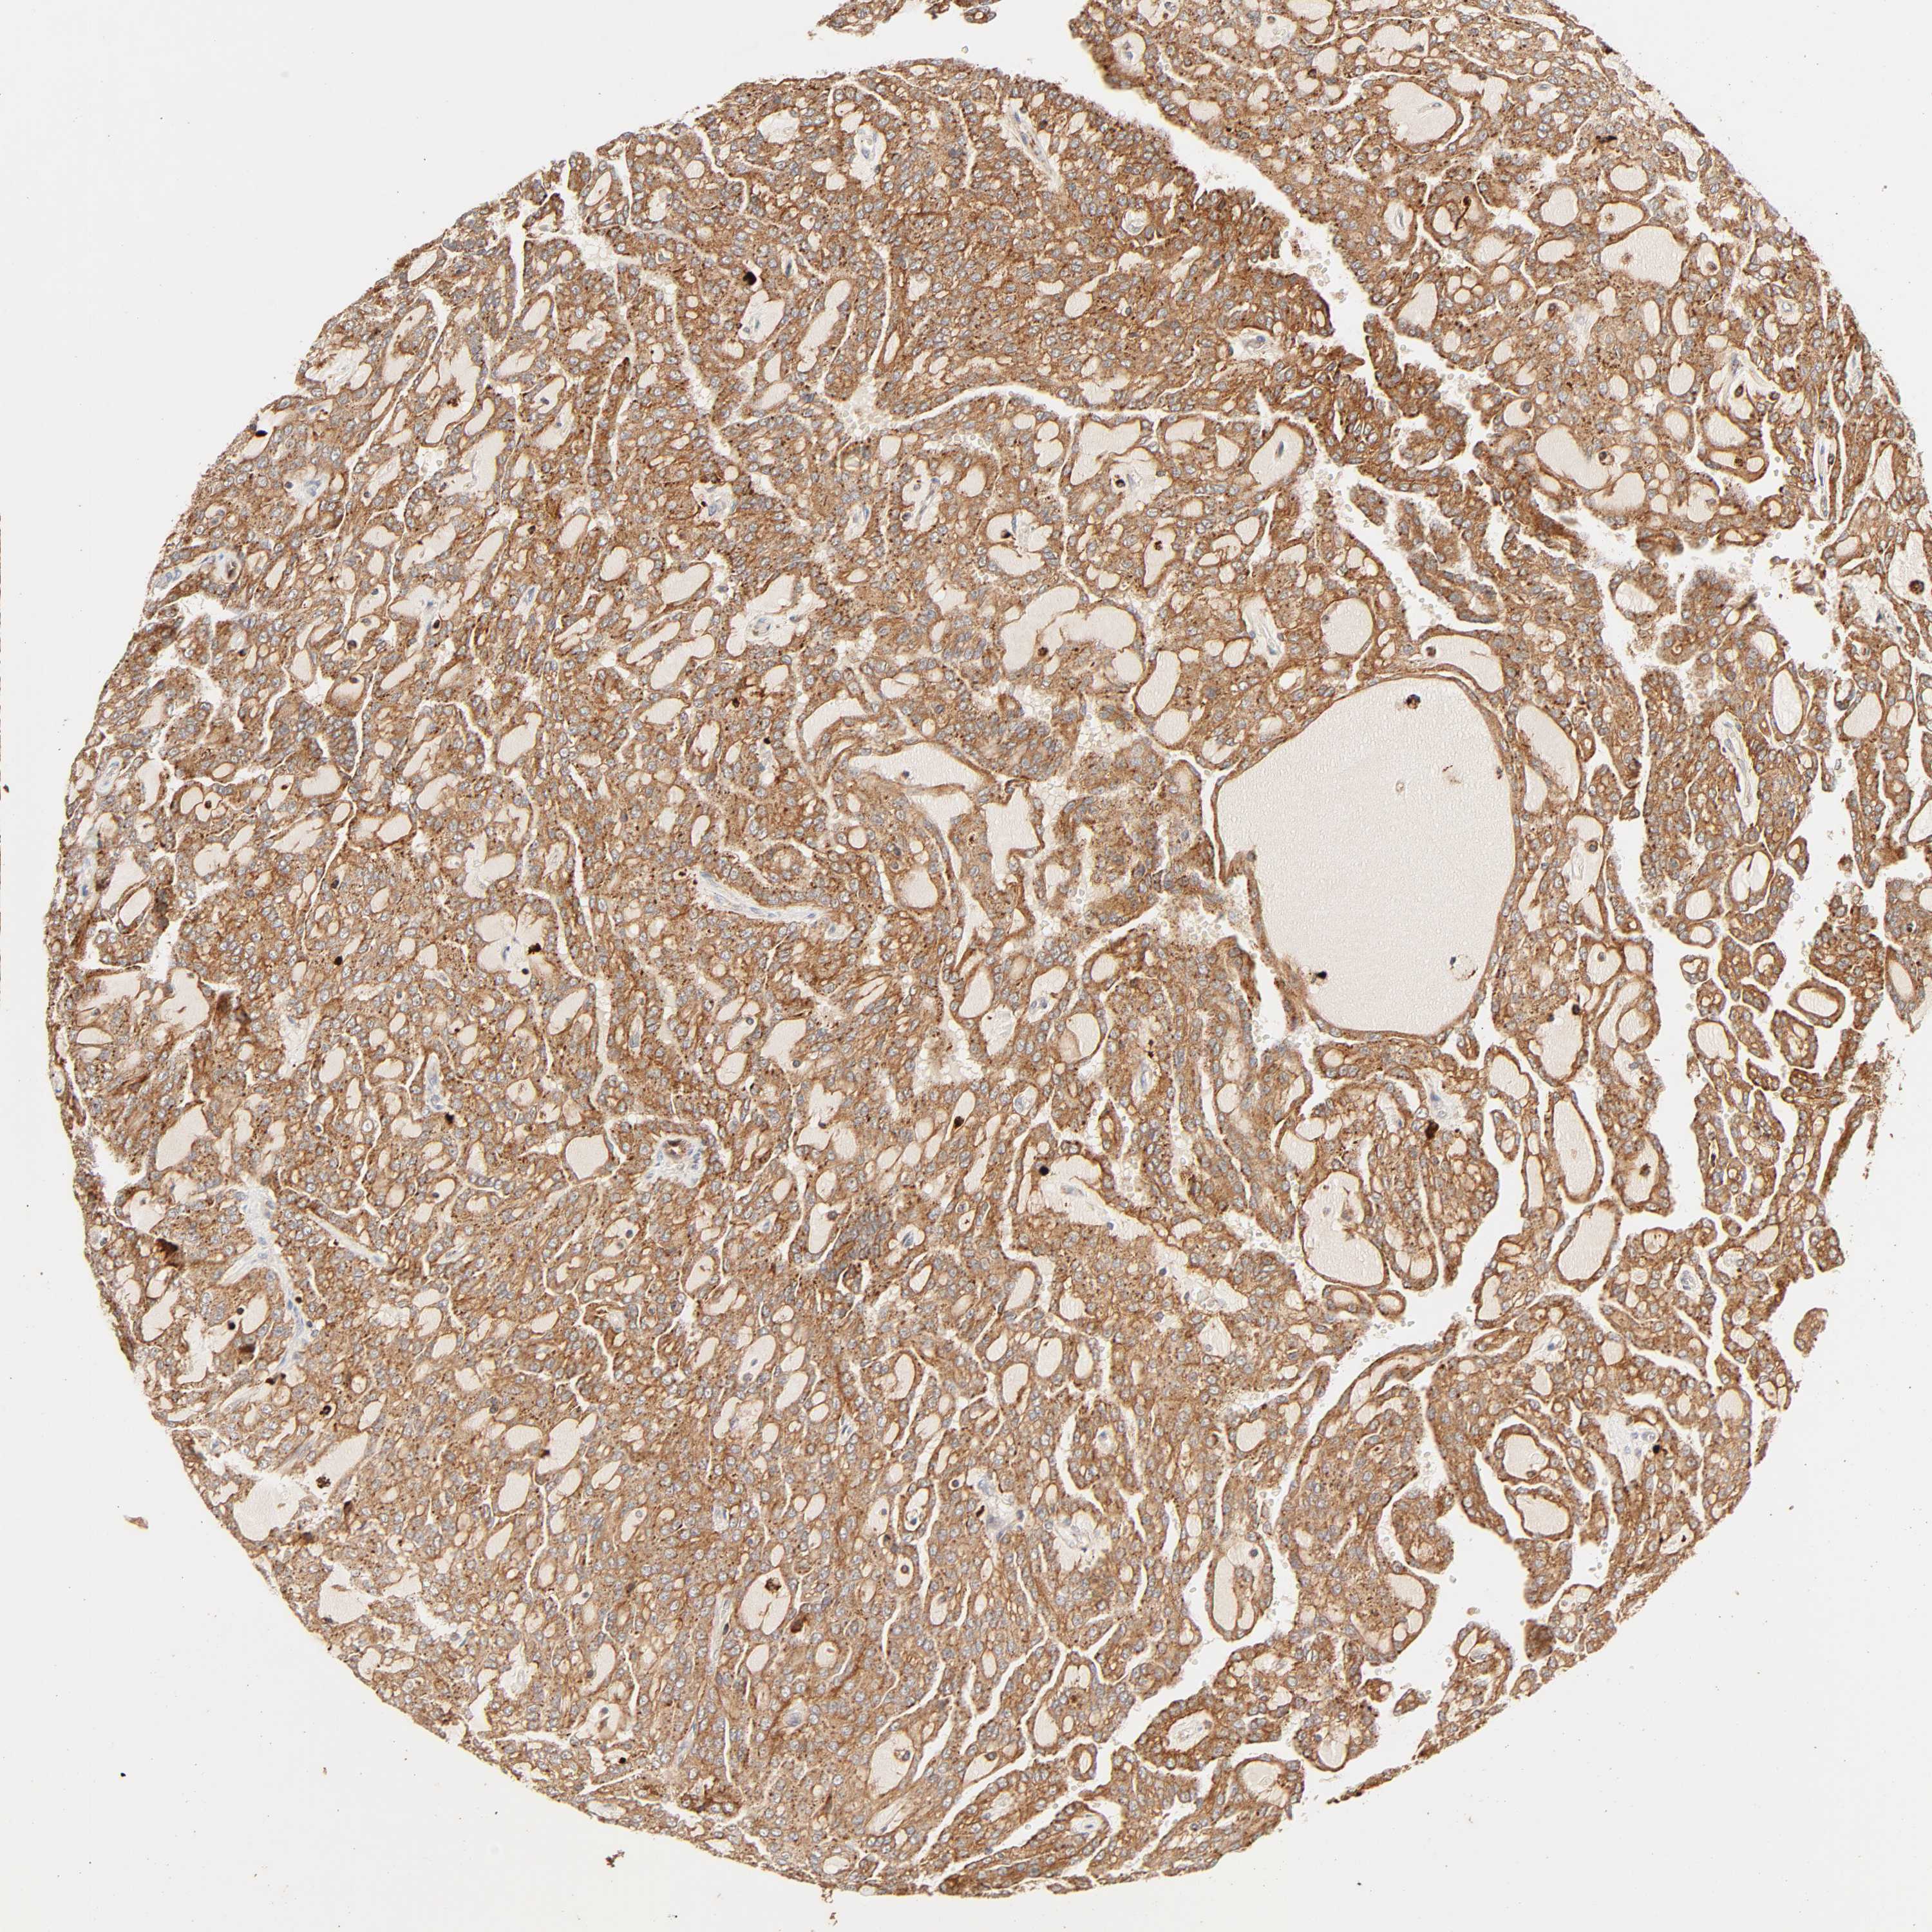

KIDNEY RENAL CLEAR CELL CARCINOMA (TCGA) - Interactive survival scatter ploti

The Survival Scatter plot shows the clinical status (i.e. dead or alive) for all individuals in the patient cohort, based on the same data that underlies the corresponding Kaplan-Meier plots. Patients that are alive at last time for follow-up are shown in blue and patients who have died during the study are shown in red.

The x-axis shows the expression levels (FPKM) of the investigated gene in the tumor tissue at the time of diagnosis. The y-axis shows the follow-up time after diagnosis (years). Both axes are complimented with kernel density curves demonstrating the data density over the axes. The top density plot shows the expression levels (FPKM) distribution among dead (red) and alive patients (blue). The right density plot shows the data density of the survived years of dead patients with high and low expression levels respectively, stratified using the cutoff indicated by the vertical dashed line through the Survival Scatter plot. This cutoff is automatically defined based on the FPKM cutoff that minimizes the p-score. The cutoff can be changed by dragging the vertical line or by entering a cutoff value in the square labeled "Current cut-off".

Under the Survival Scatter plot the p-score landscape (black curve; left axis) is shown together with dead median separation (red curve; right axis). Dead median separation is the difference in median mRNA expression between patients who have died with high and low expression, respectively. It is calculated as follows: median FPKM expression of dead patients with high expression - median FPKM expression of dead patients with low expression. This is intended to aid the user in visually exploring custom cutoffs and the associated p-scores and dead median separation.

Individual patient data is displayed and can be filtered by clicking on one or more of the category buttons on the top of the page. Categories describing expression level and patient information include: high, low, alive, dead, female, male and tumor stages. The scale of the x-axis can be toggled between linear and log-scale by clicking on the "x log" button. Mouse-over function shows TCGA ID, patient information and mRNA expression (FPKM) for each patient.

& Survival analysisi

Kaplan-Meier plots summarize results from analysis of correlation between mRNA expression level and patient survival. Patients were divided based on level of expression into one of the two groups "low" (under cut off) or "high" (over cut off). X-axis shows time for survival (years) and y-axis shows the probability of survival, where 1.0 corresponds to 100 percent.

MAPK6 is not prognostic in Kidney Renal Clear Cell Carcinoma (TCGA)

Best expression cut offi

Based on the FPKM value of each gene, patients were classified into two groups and association between prognosis (survival) and gene expression (FPKM) was examined. The best expression cut-off refers the FPKM value that yields maximal difference with regard to survival between the two groups at the lowest log-rank P-value. Best expression cut-off was selected based on survival analysis .

When clicking on this number, the vertical dashed line indicating cut-off, the interactive survival plot, and the Kaplan-Meier curve will be adjusted to show results based on the best expression cut-off.

: 7.78

Median expressioni

Median expression refers to the median FPKM value calculated based on the gene expression (FPKM) data from all patients in this dataset. When clicking on this number, the vertical dashed line indicating cut-off, the interactive survival plot, and the Kaplan-Meier curve will be adjusted to show results based on the median expression.

: N/A

Median follow up timei

Median follow up time refers to the median time (years) after diagnosis with this type of cancer, based on clinical data from all patients in this dataset.

P scorei

Log-rank P value for Kaplan-Meier plot showing results from analysis of correlation between mRNA expression level and patient survival.

N/A

5-year survival highi

5-year survival for patients with higher expression than the expression cutoff.

For melanoma and glioma, 3-year survival is shown.

5-year survival lowi

5-year survival for patients with lower expression than the expression cutoff.

TCGA RNA samplesi

RNA-seq data is reported as average FPKM (number Fragments Per Kilobase of exon per Million reads), generated by the The Cancer Genome Atlas (TCGA) .

Normal distribution across the dataset is visualized with box plots, shown as median and 25th and 75th percentiles. Points are displayed as outliers if they are above or below 1.5 times the interquartile range. FPKM values of the individual samples are presented next to the box plot.

Average pTPM 11.7

Number of samples 521